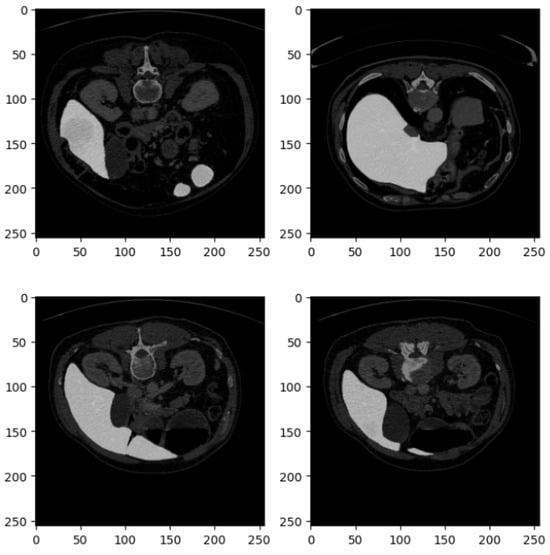

Figure 2 shows four examples of CT liver images related to the DI dataset.

Figure 2 presents four axial slices from a CT scan, likely of the abdomen. The scans are in grayscale, adhering to standard medical imaging practices. Each image slice is square with dimensions of 250 × 250 pixels, potentially corresponding to a specific magnification level or scale within the imaging modality. These slices represent axial (cross-sectional) views of the abdomen, showcasing various abdominal organs, including the liver, kidneys, stomach, intestines, and possibly sections of the spine and abdominal musculature.

In the top left image, sections of the liver (on the left side) and the kidney (on the right side) are visible, with part of the spinal column centrally located. The top right image depicts a slightly lower section of the abdomen, where the liver occupies a larger portion of the view, and a section of the bowel is observable. The bottom left slice reveals a broader section of the abdominal cavity, with distinct bowel loops that may show gas-filled intestines or contrast material. The bottom right image features the liver more prominently, extending across the section, and includes parts of the gastrointestinal system, possibly the colon.

The images appear to be contrast-enhanced, as indicated by the bright white regions representing areas of high contrast uptake, such as blood vessels or perfused organs. The overall quality of the images is high, with minimal noise, suggesting that they were acquired at an adequate resolution suitable for diagnostic or research purposes. The grayscale intensity is consistent across all slices, indicating uniform windowing and leveling, which is essential for evaluating the radiodensity of the tissues depicted.